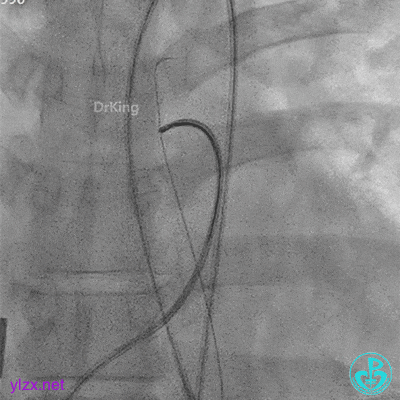

建立动静脉轨道

由导丝建立完整动静脉轨道,以便后续手术沿导丝轨道将全降解封堵器系统鞘管送入左心室。